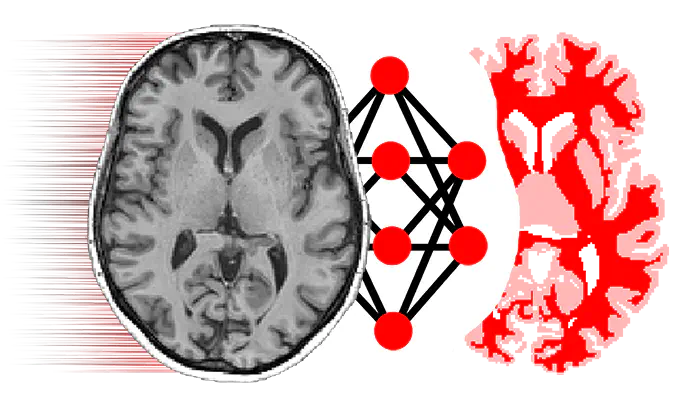

NiftyNetNiftyNet is a TensorFlow-based open-source convolutional neural networks (CNN) platform for research in medical image analysis and image-guided therapy. NiftyNet’s modular structure is designed for sharing networks and pre-trained models. Using this modular structure you can: